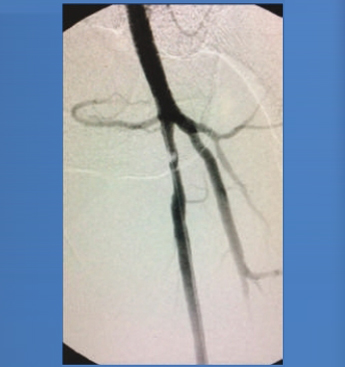

Clinical Case, SFA Lesion

PREPOST